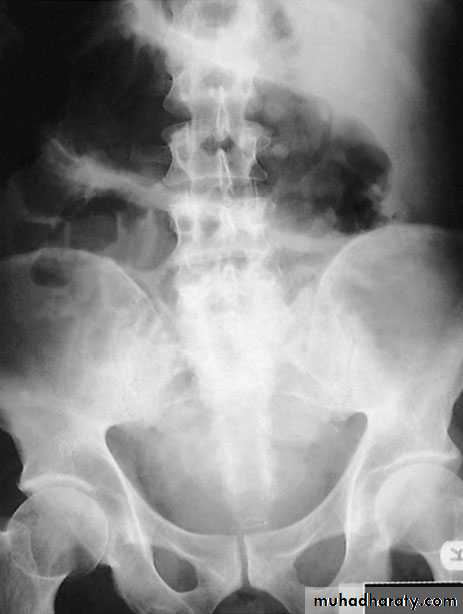

Complications of severe diseaseFulminating colitis and toxic dilatation (megacolon)Patients with severe disease should be admitted to hospital forintensive treatment. This occurs in 5–10% of patients. Thepatient will have severe rectal symptoms with systemic upset suchas weight loss and dehydration. In patients on intensive treatment such as steroids, there may befew symptoms. The diagnosis is confirmed by the presence on aplain abdominal radiograph of the colon with a diameter of morethan 6 cm. The condition must be differentiated from dysentery,typhoid and amoebic colitis. Plain abdominal radiographs shouldbe obtained daily in patients with severe colitis, and a progressiveincrease in diameter in spite of medical therapy is an indicationfor surgery

Severe attacksThese patients must be regarded as medical emergencies andrequire immediate admission to hospital. It is important to monitor vital signs (pulse, temperature andblood pressure). A stool chart should be kept.Increasing abdominal girth is a potential sign of megacolon developing.A plain abdominal radiograph is taken daily and inspectedfor dilatation of the transverse colon of more than 5.5 cm.

The presence of mucosal islands or intramural gas on plain radiographs increasing colonic diameter or a sudden increasein pulse and temperature may indicate a colonic perforation. Fluidand electrolyte balance is maintained, anaemia is corrected andadequate nutrition is provided, parenteral nutrition may be indicated.The patient is treated with intravenous hydrocortisone100–200 mg four times daily.